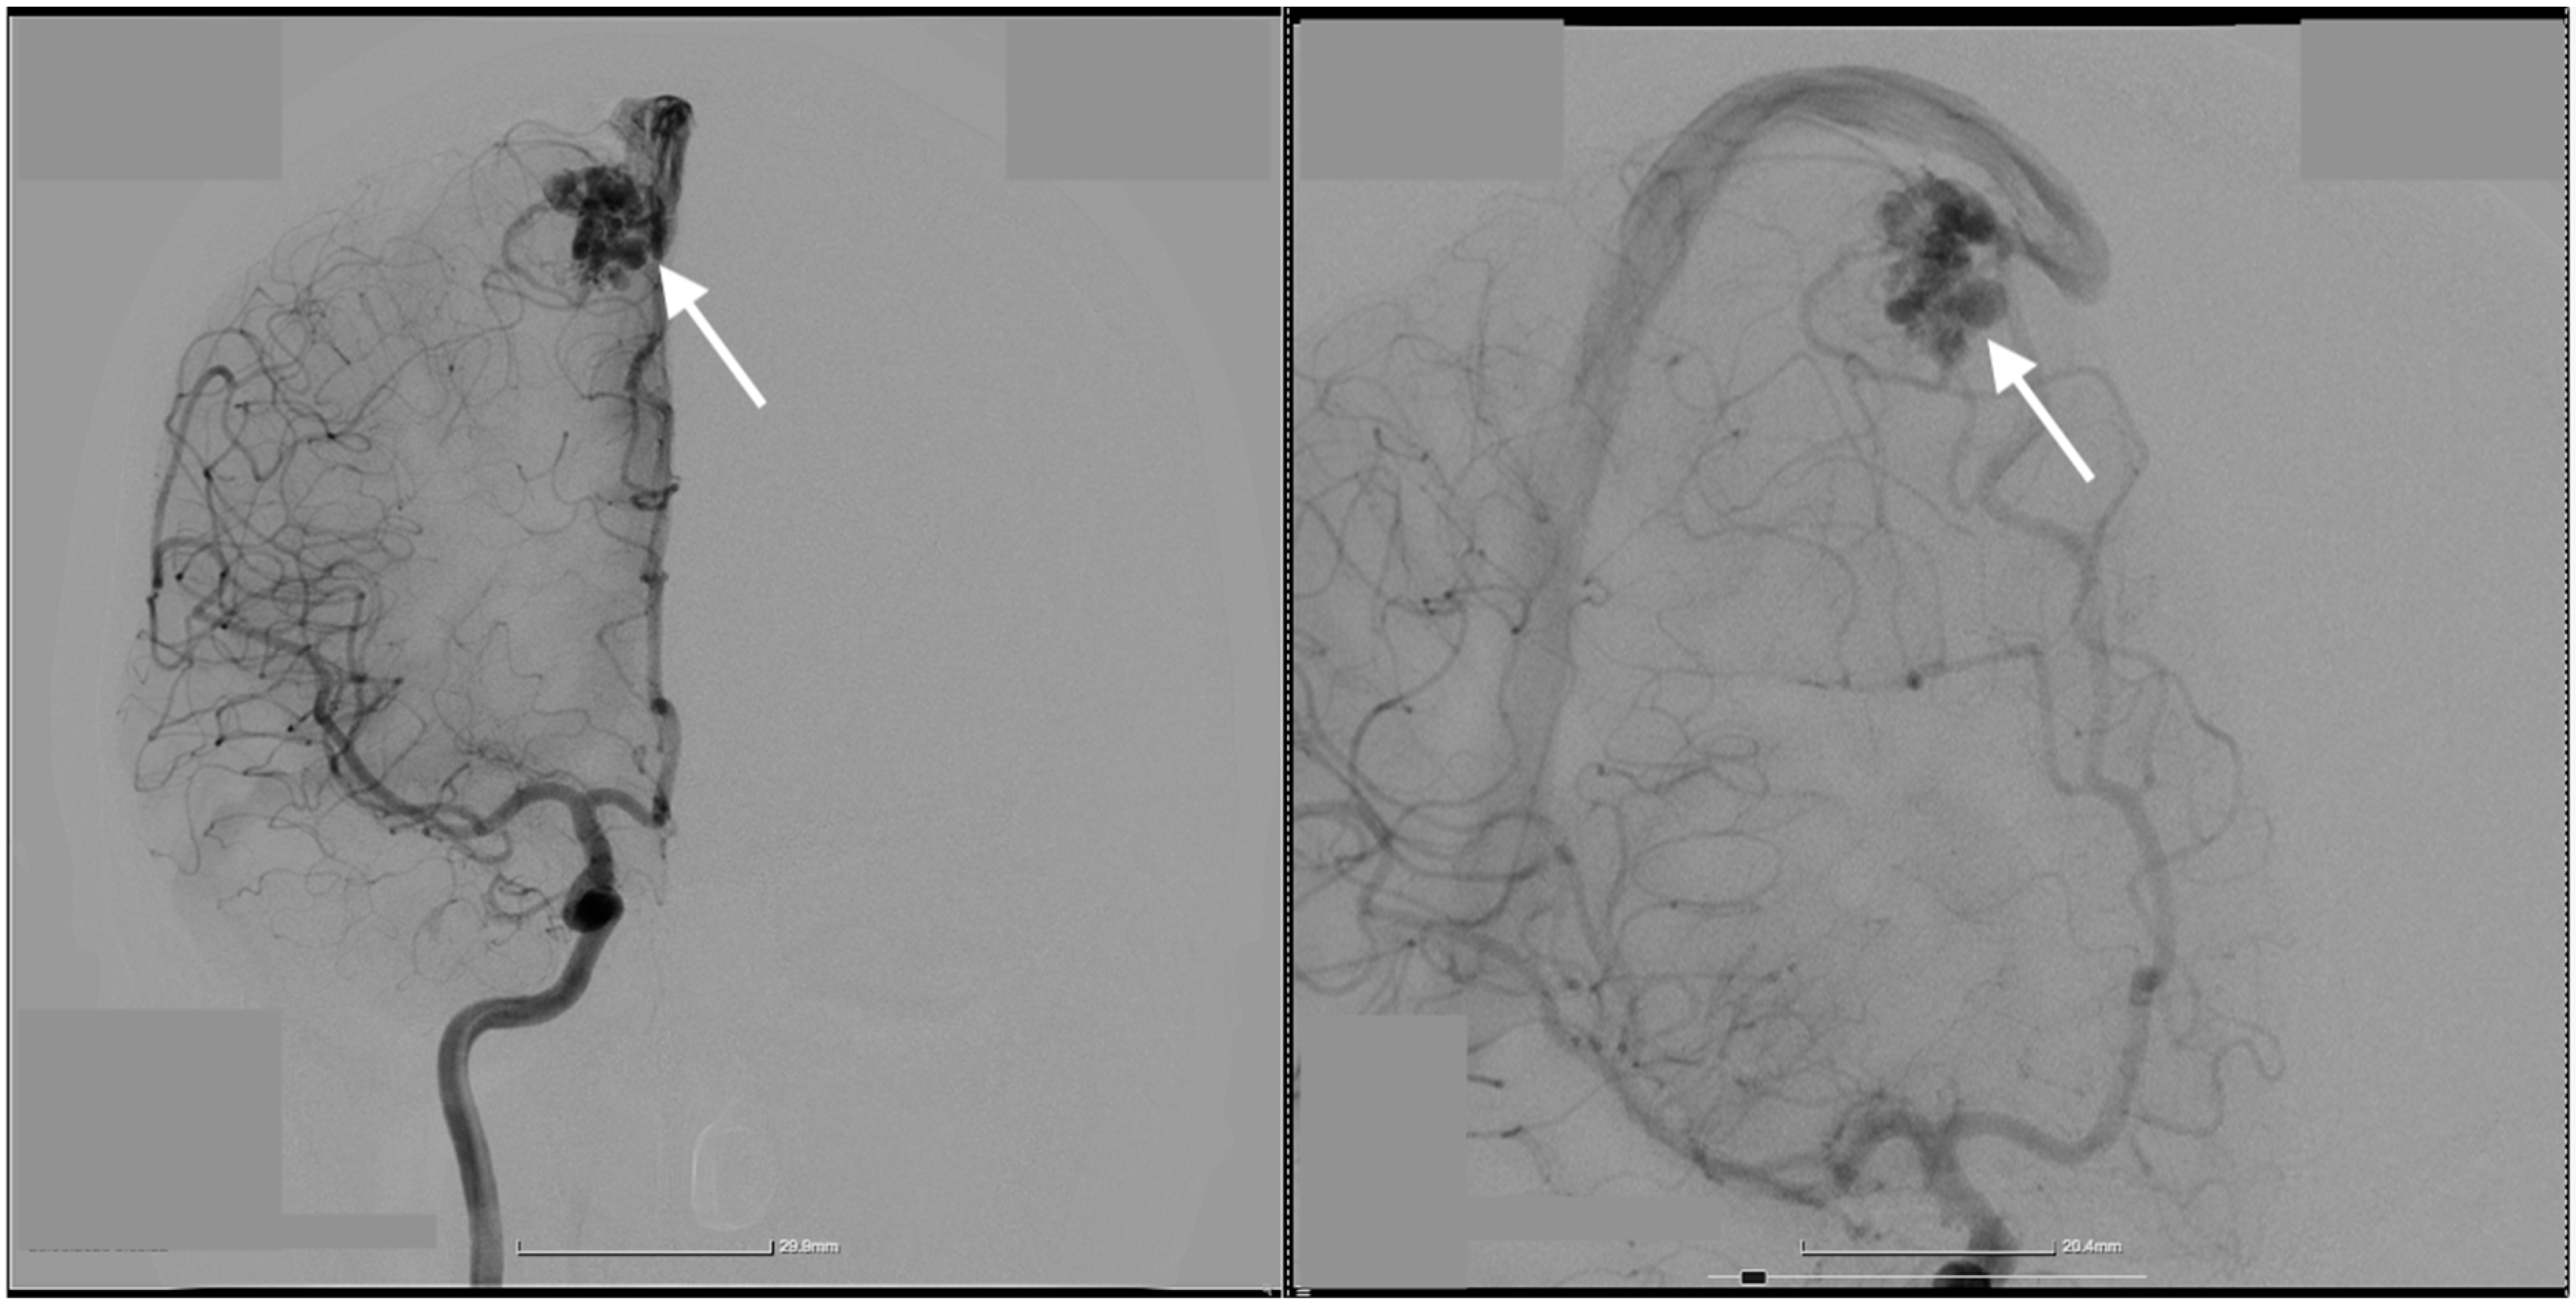

2. Case Presentation